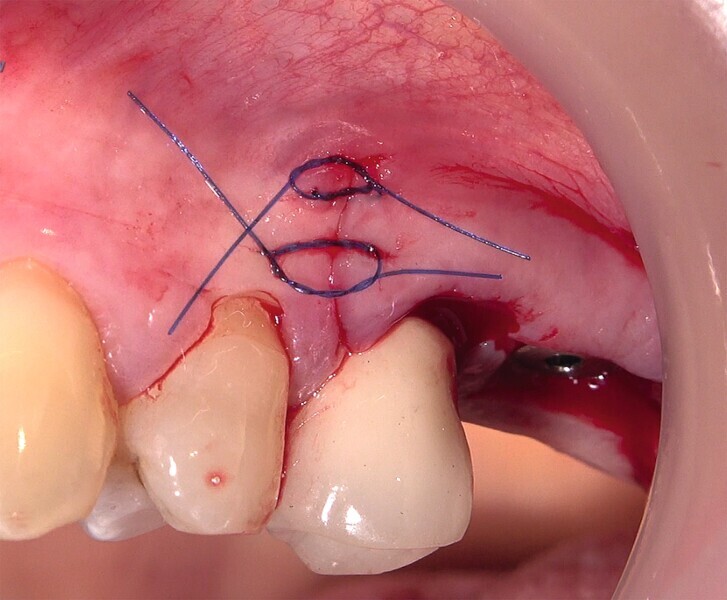

Fig. 31 : Mise en place d’une membrane de collagène à titre de barrière de protection et suture.

Fig. 32 : Mise en place d’une membrane de collagène à titre de barrière de protection et suture.

Fig. 33 : Mise en place d’une membrane de collagène à titre de barrière de protection et suture.

La crête alvéolaire au niveau du site de la molaire inférieure était trop étroite pour permettre la pose prédictible d’un implant sans une augmentation osseuse préalable. Des implants deux pièces en zircone ont été mis en place, simultanément à une augmentation osseuse latérale, au moyen d’une allogreffe et d’une membrane de collagène résorbable (Figs. 25–34).